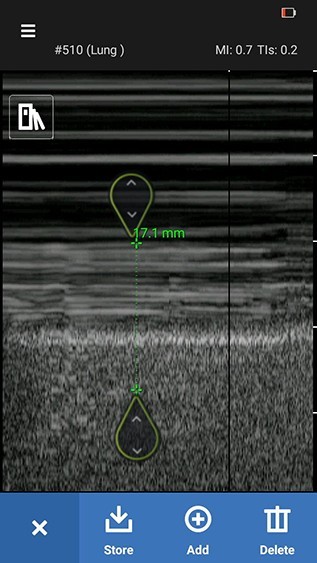

3. Vertical measurements can be performed on the M-mode image by pressing the Distance icon.

4. Press Distance icon.

Distance measurement